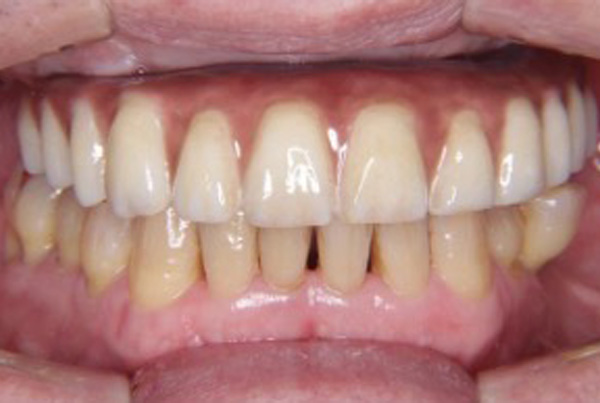

当院のオールオン4症例

初診 治療前

入れ歯を使用されていないため、食事では柔らかいものしか食べることができない状態でした。

治療後(手術当日)

たった1日で大幅に歯の状況が改善され、好きな物を何でも食べることが出来るようになりました。(プラスチック製の仮歯)

治療完了(本歯装着)

セラミックの本歯が入り、治療前は食べることが出来なかった固いものなど、好きなものを気にせずに何でも食べることが出来るようになりました。見た目も患者様の理想的な形で、本物の歯と歯肉のような艶や透明感があります。

当院のオールオン4ではここまで綺麗になります

上記の写真をご覧いただければお分かりいただける通り、オールオン4ではお口の状況が大幅に改善されます。